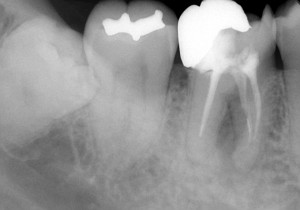

レントゲン写真で確認すると

根の先に病気がある。かぶせ物の適合も悪そう。

そして・・・

う~ん・・・(汗) どうも治療器具が折れて中に残っていそう(T_T) そのため、根の先まで治療が行えていない。